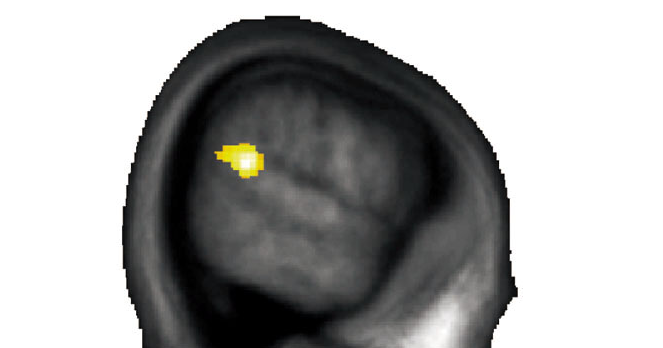

Das Ziel der Studie war jedoch herauszufinden, warum es solche Unterschiede gibt. Frühere Studien legten dar, dass eine bestimmte Hirnregion – die Übergangsregion zwischen dem Scheitel- und dem Schläfenlappen – mit der Fähigkeit zusammenhängt, sich in die Lage anderer Menschen hineinzuversetzen, um ihre Gefühle und Gedanken zu verstehen. Altruismus wiederum hängt mit dieser Fähigkeit wahrscheinlich eng zusammen. Daher vermuteten die Forschenden, dass individuelle Unterschiede in dieser Grenzregion mit unterschiedlichem altruistischen Verhalten zusammenhängen. Was laut Yosuke Morishima, Postdoktorand am Institut für Volkswirtschaftslehre der Universität Zürich, der Fall ist: «Personen, die sich altruistischer verhielten, wiesen auch mehr graue Hirnsubstanz in der Übergangsregion zwischen Scheitel- und Schläfenlappen auf.»

Während ihrer Entscheidungen zur Geldteilung zeigten die Studienteilnehmenden auch deutliche Unterschiede in ihrer Hirnaktivität. Bei egoistischen Personen ist die kleine Hirnregion hinter dem Ohr schon bei geringen Kosten einer altruistischen Handlung aktiv. Bei altruistischen Personen hingegen wird diese Hirnregion erst stärker aktiv, wenn diese Kosten bereits sehr hoch sind. Die Hirnregion ist folglich dann besonders stark aktiviert, wenn Menschen an die Grenzen ihrer Bereitschaft gelangen, altruistisch zu handeln. Weil zu diesem Zeitpunkt, so vermuten die Forschenden, die größte Notwendigkeit besteht, den natürlichen Egozentrismus des Menschen durch Aktivierung dieser Hirnregion zu überwinden.